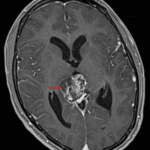

Age: 17

Sex: Male

Indication: Diplopia

MRI

Teratoma (pineal region)